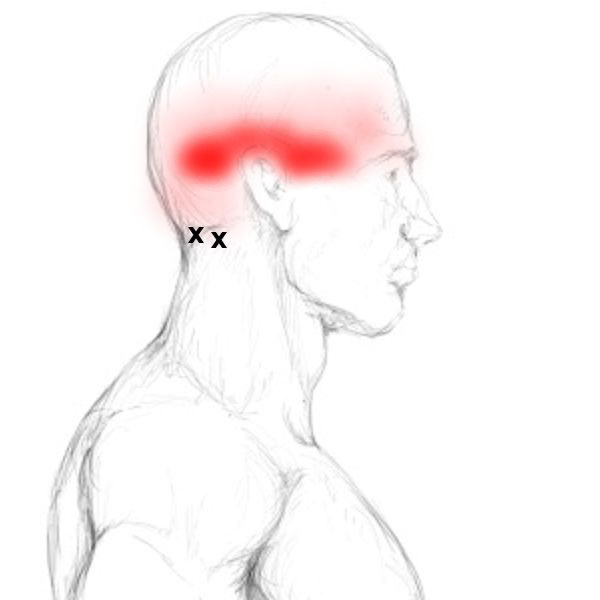

Μια κοινή υπόθεση είναι ότι οι πονοκέφαλοι προέρχονται από το εσωτερικό του κεφαλιού μας, αλλά συχνά προέρχονται από τον αυχένα. Ένας ιδιαίτερα κοινός τύπος – είναι οι υπινιακοί πονοκέφαλοι.

Το ινιακό, με απλά λόγια, είναι το πίσω μέρος του κεφαλιού. Οι υπινιακοί μύες είναι οι μύες που βρίσκονται στον ινιακό.

Αυτοί οι μύες μπορεί να είναι σφιγμένοι, κάτι που μπορεί να οδηγήσει σε πονοκεφάλους στο πίσω μέρος του κεφαλιού και ακόμη και στο μπροστινό μέρος, σε όλο το μέτωπο.

Μπορείτε να ασκείσετε πίεση με 1 ή 2 δάκτυλα και κάνοντας κυκλική κίνηση, στο πίσω μέρος του κεφαλιού. 30-60 δευτερόλεπτα σε κάθε πλευρά μία φορά την ημέρα θα πρέπει να είναι αρκετά για να δείτε μια αξιοσημείωτη βελτίωση μέσα σε λίγες μέρες, αν και θα είναι λίγο άβολο. Εάν είναι πολύ ευαίσθητοτο σημείο, δεν θα συνιστούσαμε να το κάνετε πολύ περισσότερο από αυτό, καθώς, ενώ μπορεί να είναι ακόμα αποτελεσματικό, μπορεί επίσης να προκαλέσει πονοκεφάλους για μερικές μέρες μετά.